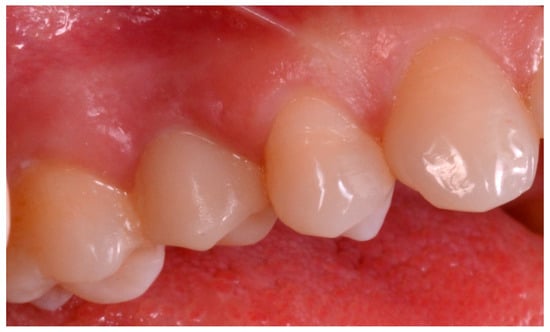

The patient sat on the dental chair (Figure 6) and rinsed 3 or 4 time with chlorexidine 0.2% mouthwash, 10 min before surgery, for a total of 2 min.

Figure 6.

Pre-operative situation. (A) Occlusal view. (B) Lateral view.